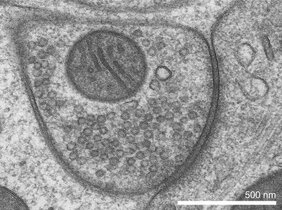

Das VGAT-Gen enthält den Bauplan für einen molekularen Transporter im Gehirn, der den wichtigen Botenstoff GABA in die Botenstoffbehälter innerhalb einer Nervenzelle – die sogenannten synaptischen Vesikel – transportiert. Dort wird GABA aufbewahrt und ausgeschüttet, wenn ein Signal an eine benachbarte Zelle weitergeleitet werden soll.